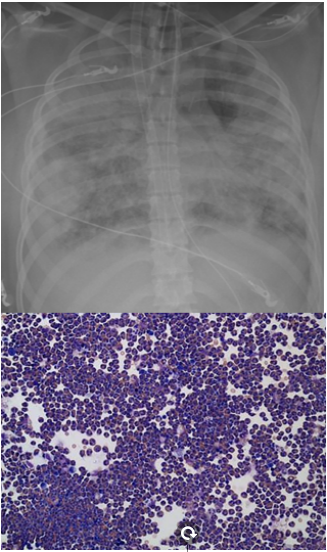

病例1:65岁女性,既往体健,活动后呼吸困难7天,加重5天,于2023年3月8日入院。入院后发热,P/F 130 mmHg。血常规:WBC 7.24×109/L,NEU 6.42×109/L,LYM 0.55×109/L,CRP 95.21 mg/L。PCT<0.02 ng/ml。BALF NGS:甲型流感病毒(序列数28947),烟曲霉(序列数26),肺炎链球菌(序列数78)。甲型流感病毒核酸检测阳性,新甲型H1N1流感病毒核酸检测阳性。予哌拉西林他唑巴坦+奥司他韦+伏立康唑抗感染治疗。然而,患者在靶向抗感染治疗下,氧合和影像进行性恶化(图4)。这种治疗效果完全不符合我们初始的预判。

图片

图4  患者影像学变化

预后:患者影像学表现(图6)和氧合逐渐改善,最终撤离ECMO。

图6  治疗后患者胸部CT